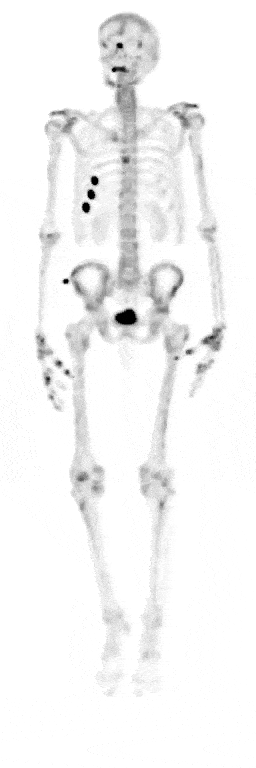

BADANIA SCYNTYGRAFICZNE SPECT/CT